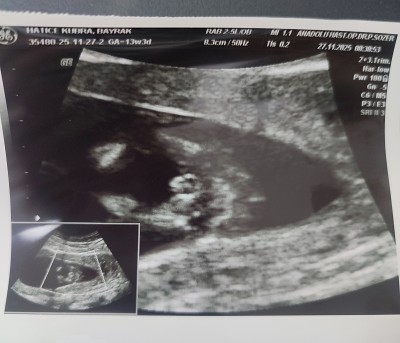

11 haftalık ve 13+5 haftalık ultrason görüntülerimiz doktor cinsiyette emin olamadi önce erkek sonra kız dedi ama sizin tahminleriniz neler?

Gebelik haftası 13+5

Bacak arasında uç cızgı var gıbı canm kıza benzettim bende